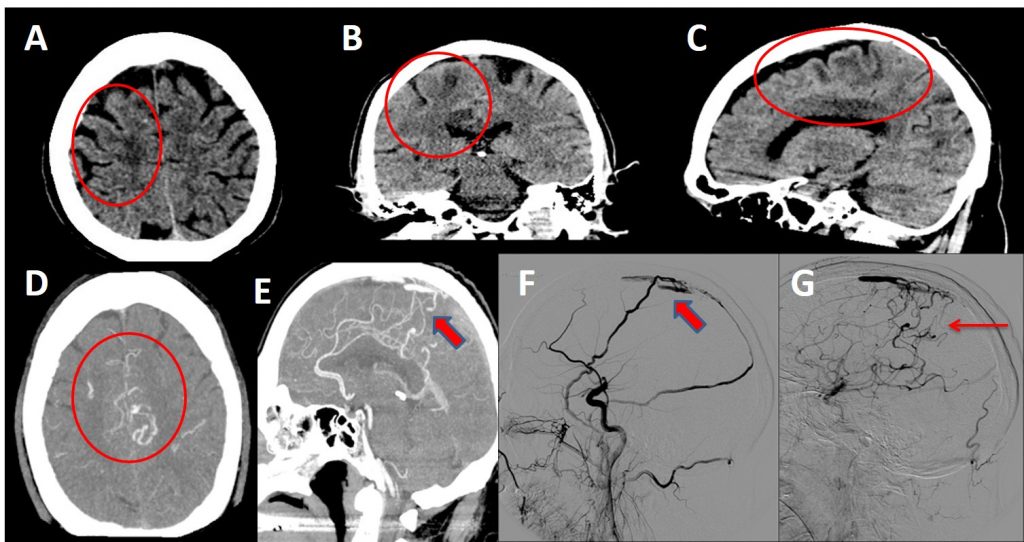

A-B-C. Cortes axial, coronal y sagital de TC craneal sin contraste donde se visualizan áreas de hipodensidad con patrón vasogénico en sustancia blanca subcortical de la circunvolución del cíngulo y frontal superior derechas, así como estructuras vasculares serpiginosas hiperdensas en los surcos adyacentes.

D-E. ANGIOTC arterial donde se observa una abundancia de vasos arteriales piales de pequeño calibre en los surcos de ambas regiones perirolándicas. Relleno precoz de algunas de las venas corticales de drenaje del vértex y parasagitales, que abocan y rellenan precozmente el tercio medio del seno sagital superior.

F-G. Arteriografía selectiva de ACC derecha donde se observan ramas frontal y parietal de arteria meníngea media derecha comunicando con tercio medio del seno sagital superior, produciendo su relleno precoz a dicho nivel, con drenaje a venas corticales dilatadas y ectásicas.